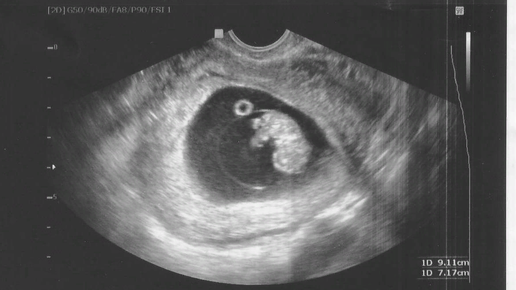

На УЗИ не видно сердцебиение плода. Это повод для тревоги?

На первом УЗИ на ранних сроках беременности женщина может столкнуться с проблемой — врач не увидел сердцебиение плода. Почему это происходит? На какой неделе у плода появляется сердцебиение? В каком случае его отсутствие может означать, что плод не развивается? Гинеколог клиники DocMed Ольга Федотова ответила на эти вопросы. На какой неделе беременности у плода появляется сердцебиение? ​​Сердцебиение появляется у плода на пятой-шестой неделе беременности, когда эмбрион достигает размера трех-шести миллиметров...